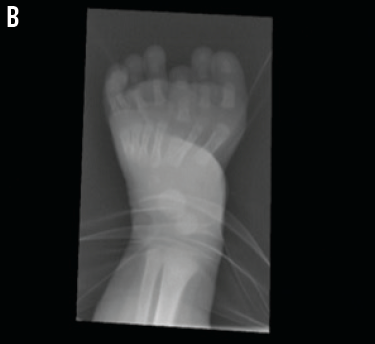

In this newborn with atypical polydactyly, an orthopedic surgeon commented on her “mirror foot” with an abnormal metatarsal region and foreshortened third metatarsal, increasing the complexity of her case (B). Surgical plans eventually may entail removal of the third and lateral rays and the abnormal third metatarsal when the girl is approximately 1 year of age. A repeat anteroposterior radiograph of her foot was scheduled for 9 months of age to evaluate for “new” bones that may have ossified since her first radiograph, which ultimately may affect surgical planning.